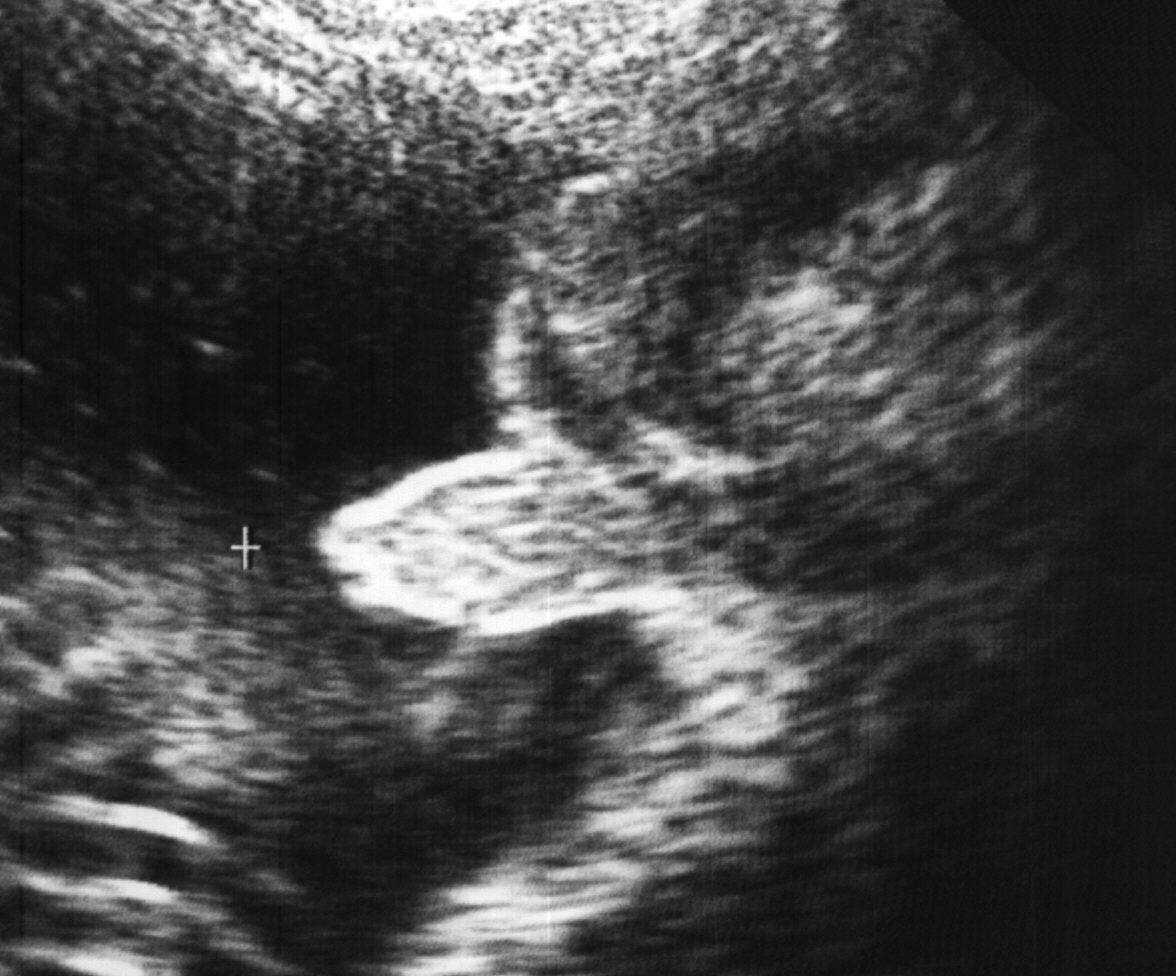

/ 10Zdjęcia płodu - serce

Płód w 25 tygodniu ciąży, na zdjęciu widoczne serce dziecka